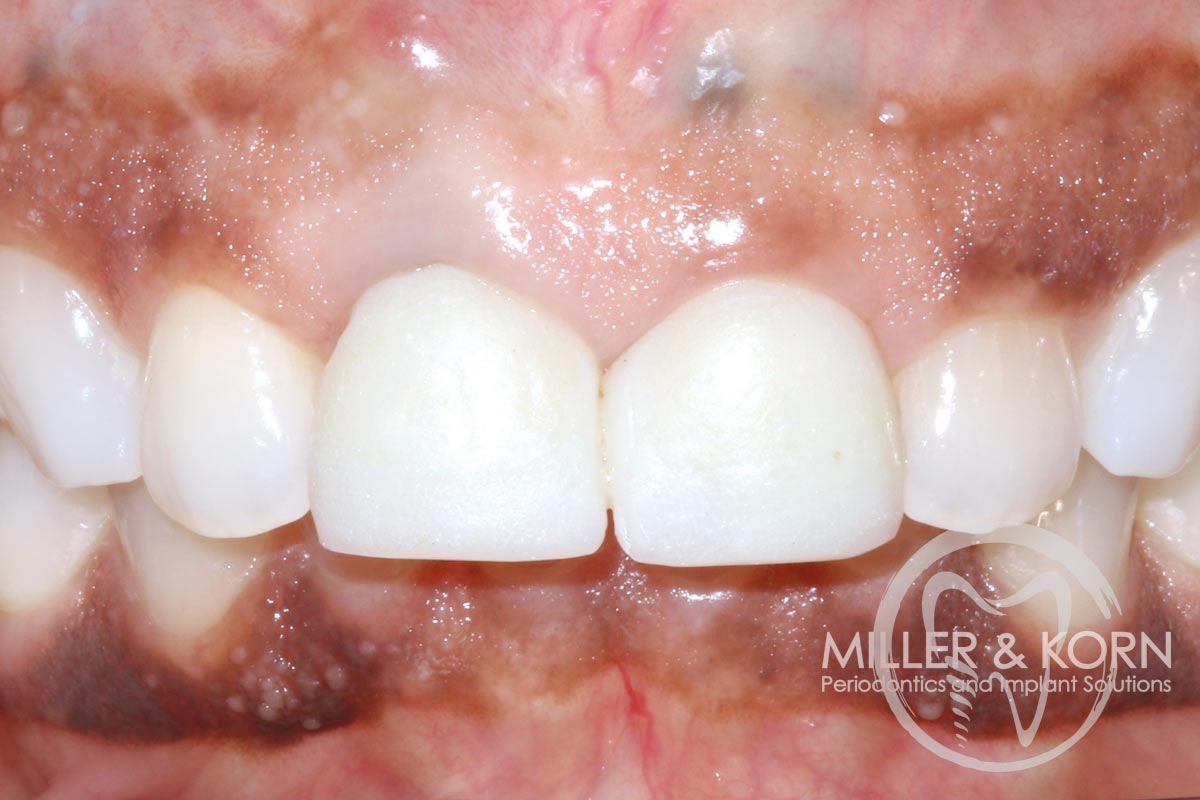

1/22 - 60-year-old female patient presented with a chronic infection on tooth #11. Since she has a high lip line matching the gingival margins of the adjacent central incisor and creating a root eminence is extremely important. For these reasons, the treatment of choice was an allograft bone ring enabling immediate placement of the dental implant with simultaneous regeneration of her ridge.Immediate implant placement and regeneration of ridge using an allograft bone ring and Jason® membrane - Drs. Miller and Korn

2/22 - She experienced trauma as a child and had fractured both tooth #8 and 9 which had been crown several times for esthetics.Immediate implant placement and regeneration of ridge using an allograft bone ring and Jason® membrane - Drs. Miller and Korn

60-year-old female patient presented with a chronic infection on tooth #11.

Since she has a high lip line matching the gingival margins of the adjacent central incisor and creating a root eminence is extremely important. For these reasons, the treatment of choice was an allograft bone ring enabling immediate placement of the dental implant with simultaneous regeneration of her ridge.